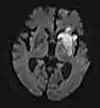

Diffusion weighted (DWI)ConventionalDWIMeasure of Brownian motion of water molecules.[78] High signal within minutes of cerebral infarction (pictured).[79]

Apparent diffusion coefficientADCReduced T2 weighting by taking multiple conventional DWI images with different DWI weighting, and the change corresponds to diffusion.[80] Low signal minutes after cerebral infarction (pictured).[81]